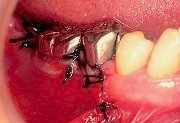

5

| 添付されている吸収性の縫合糸を用い、歯面と緊密に接する様に注意しながら歯牙へ固定してゆく。メンブレン固定後はプローブ等を用いて歯面との間に上皮が入るスペースがないことを確認しておく。 |